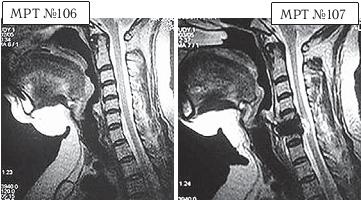

На МРТ № 106 состояние шейного отдела пациентки до операции. Наблюдается сглаженность физиологического лордоза, ликворные пути свободны, компенсированные протрузии межпозвонковых дисков в сегментах СIII—СIV

На МРТ № 107 состояние шейного отдела той же пациентки после дискэктомии с межтеловым спондилодезом в сегменте CV—CVI, кроме того наблюдается травма спинного мозга на данном уровне хирургической фрезой.

Если до операции у данной пациентки были незначительные вертебробазилярные нарушения, то после… Травма спинного мозга хирургической фрезой — это, конечно, трагическая случайность. Ведь от ошибок никто не застрахован и добросовестный врач никогда не даст гарантии на положительный исход любого вида лечения. Но в данном случае проведение самой операции было абсолютно необоснованным, фактически она превратила нормального человека в инвалида.